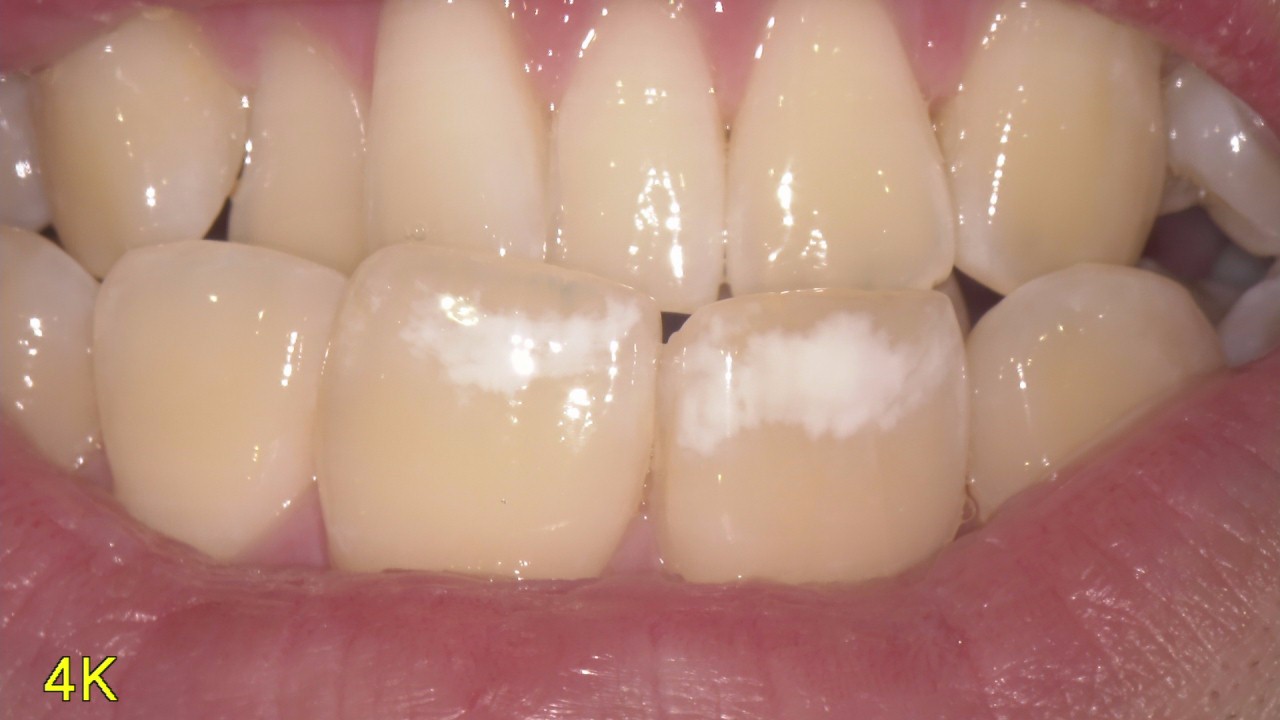

歯が白く変色している!?

歯に白く変わってるの気にしてませんか? 最近の症例をご紹介いたします! これは「ホワイトスポット」という病変です。歯が作られる過程で変色してしまった状態です。 昔はこれが気になる場合は削って詰めたりかぶせたりして色を合わ […]